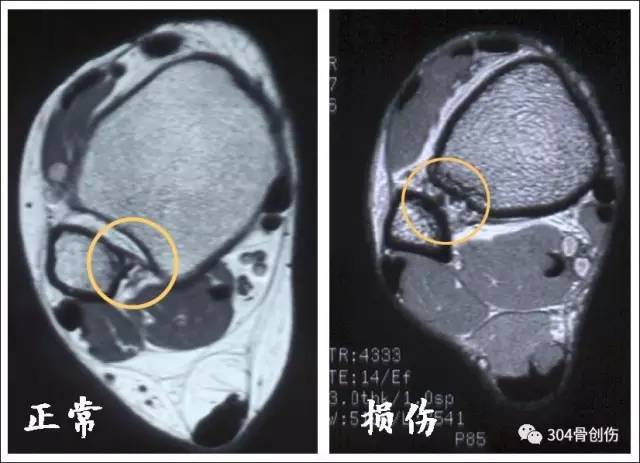

MRI 诊断

MRI能够直观看到下胫腓韧带损伤,敏感度较强,量化评价下胫腓分离逊于CT三维重建,一般CT检查足以诊断下胫腓分离,不必常规再行MRI检查,能更好节约医疗费用。

下胫腓前韧带对比

骨间韧带对比

骨间膜对比

下胫腓后韧带对比